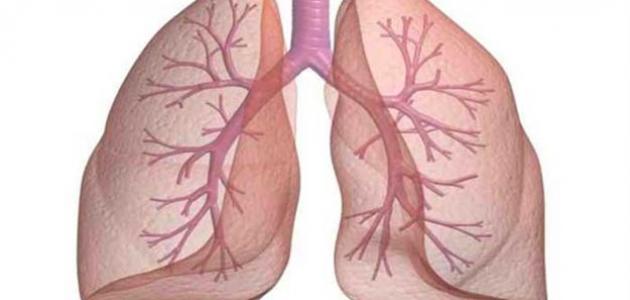

الرئتان:

تقع داخل تجويف القفص الصدري والعمود الفقاري، ويقع تحتها عضلة الحجاب الحاجز، وتحتوي على الشعيرات الدموية الرئوية والقصيبات الهوائية، ووظيفتها تبادل الغازات الناتجة عن عمليات الجسم ففيها يتم تبادل الأكسجين مع ثاني أكسيد الكربون.